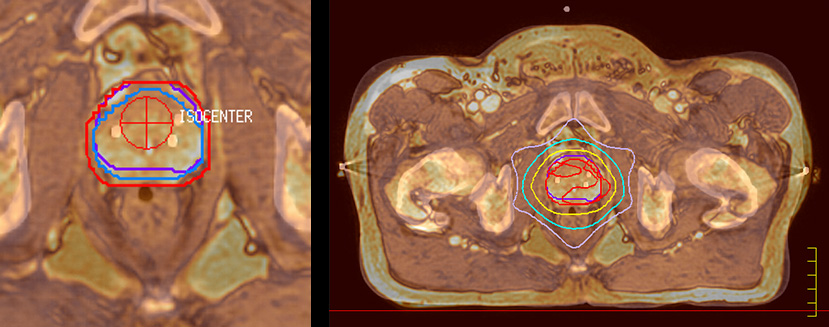

Beaumont Health System (Royal Oak, Michigan, USA) is one of the largest health systems in the USA, with eight hospitals and 153 outpatient sites, a medical school and a research institute. The Radiation Oncology (RO) department houses a dedicated Ingenia MR-RT solution that is routinely used for clinical and research MR-RT activities. “The main reason to integrate MR imaging in RT planning is the superb soft tissue contrast that allows detailed delineation of tumors and healthy organs, which is crucial for RT planning,” says Craig W. Stevens MD, PhD. “MR also provides information on functional and biological activities in tumors, background tissue and normal organs, which may also be used in RT planning,” says physicist Di Yan, DSc, FAAPM.” “We currently use MR-RT mainly in the abdomen and pelvis region: prostate, colorectal, pancreatic, cervical, and liver. Also in the brain, we are starting to use it,” says Dr. Yan.

“The biggest problem for CT-based planning, especially in prostate, is you can’t see the cancer very well,” says Dr. Stevens. “On CT it can be quite challenging to see the edge of the prostate especially at the apex. When the edge of the prostate can’t be delineated well on CT, radiation oncologists will increase their margins a little bit so they don’t miss it, but that can also increase toxicity.” “Using MR, the prostate is well delineated. We quickly see the edges of cancerous tumors like in prostate cancer, and as normal structures can be defined, we can optimize the treatment plan to protect these organs and their normal function. This can potentially improve the outcome. And it improves workflow as well. We can contour more quickly, confident that the tumor is going to be in the field.” “The Ingenia 3.0T MR scanner provides high resolution allowing us to make scans fast for the patients. It also gives the potential to include methods like MR spectroscopy and diffusion weighted Imaging, which we’re in the process of doing right now,” Dr. Stevens adds.

“When a patient registers, first CT simulation and MR simulation are done, followed by CT-MR registration on Pinnacle3. Then the target and normal organ delineation is performed on MR images. Meanwhile we create a reference CT image for online treatment and localization correction. During the treatment phase we can perform additional MRI scans to visualize the anatomy changes and create an adaptive plan. This plan basically adapts the treatment plan to the changes.” “Along with its great benefits, MR has introduced some new challenges,” Dr. Stevens says. “Radiation therapy teams generally have no experience with MR. The Philips training helped us to implement fully the things we can do with the Ingenia MR-RT system. So the training, as well as having a good MR physicist, is critical.”